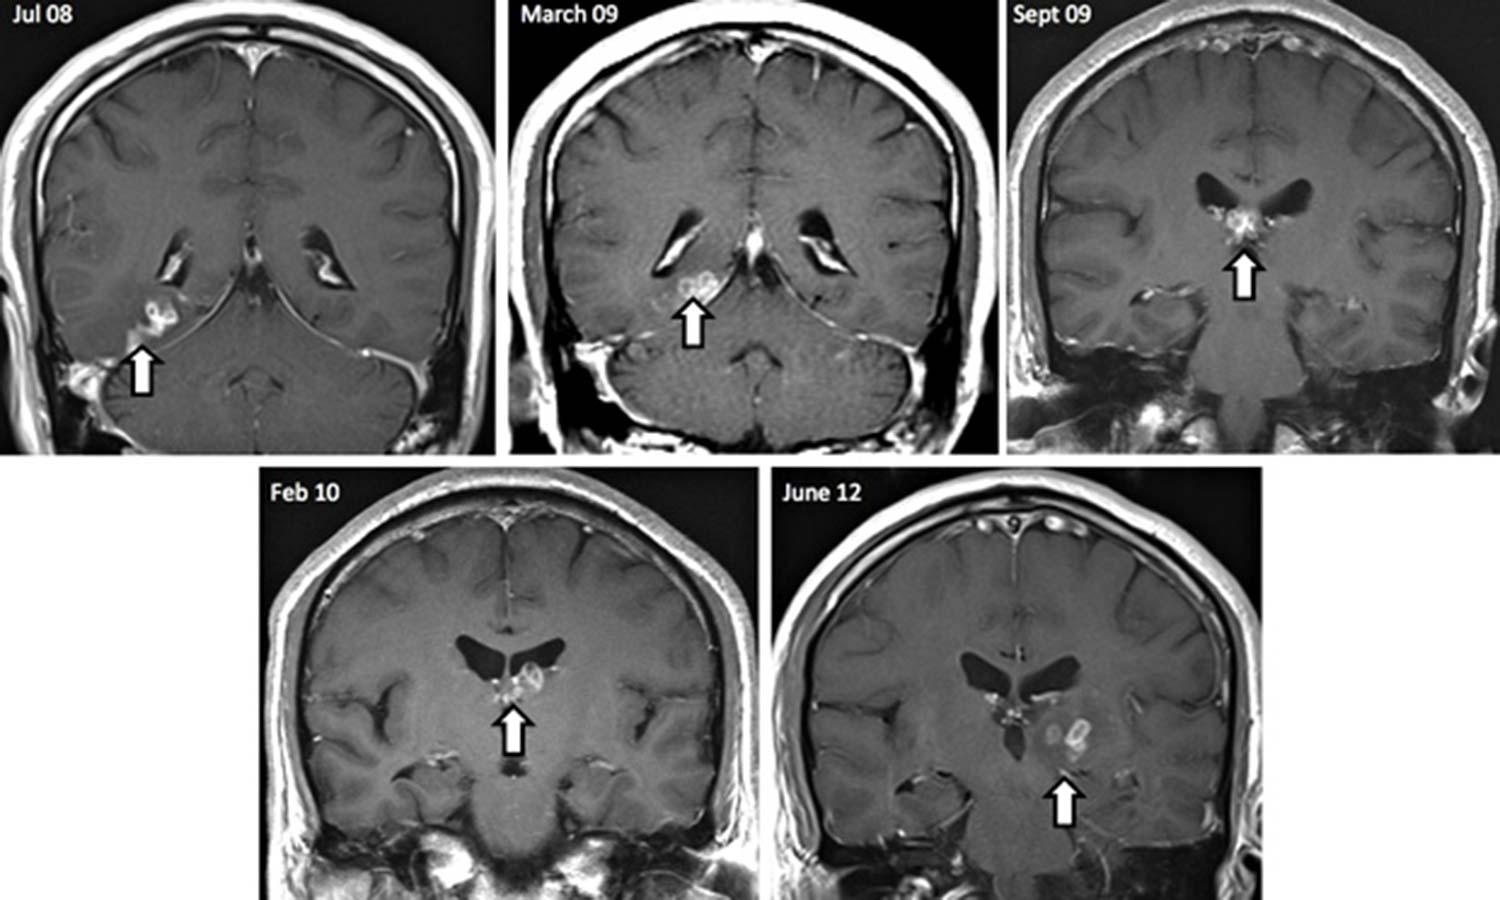

Según informó el diario británico The Guardian, un hombre de 50 años acudió al médico tras padecer fuertes dolores de cabeza y hasta olores extraños y al realizarle estudios, estos encontraron un extraño gusano acintado que se movía de un hemisferio del cerebro a otro.

Los especialistas pudieron notarlo tras realizarle varias tomografías, por lo que creen que el parásito pudo haber durado durante cuatro años y se internó en su cuerpo durante uno de sus viajes a China cuando fue a visitar a su familia.